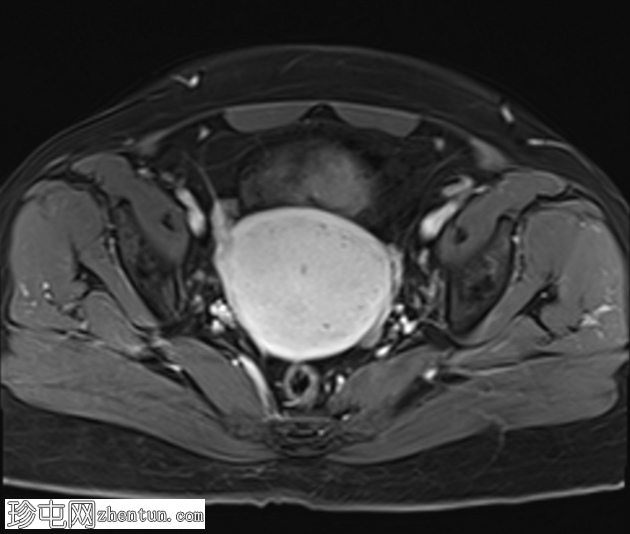

轴位

T1加权像

子宫增大,交界区弥漫性增厚,厚度约2.5 cm,边界模糊,在T1加权像和T2加权像上均可见无数点状高信号灶,提示出血灶。

在预期的膀胱尿道区域可见一小片异常信号强度的局灶性区域,T2加权像呈高信号,提示膀胱尿道子宫内膜异位症。

盆腔影像学检查(超声或MRI)通常显示局灶性或弥漫性、常不对称的子宫肌层增厚,并伴有异质性影像。

我们报告一例50岁女性患者,其超声和MRI影像均表现出弥漫性子宫腺肌症的特征性表现。